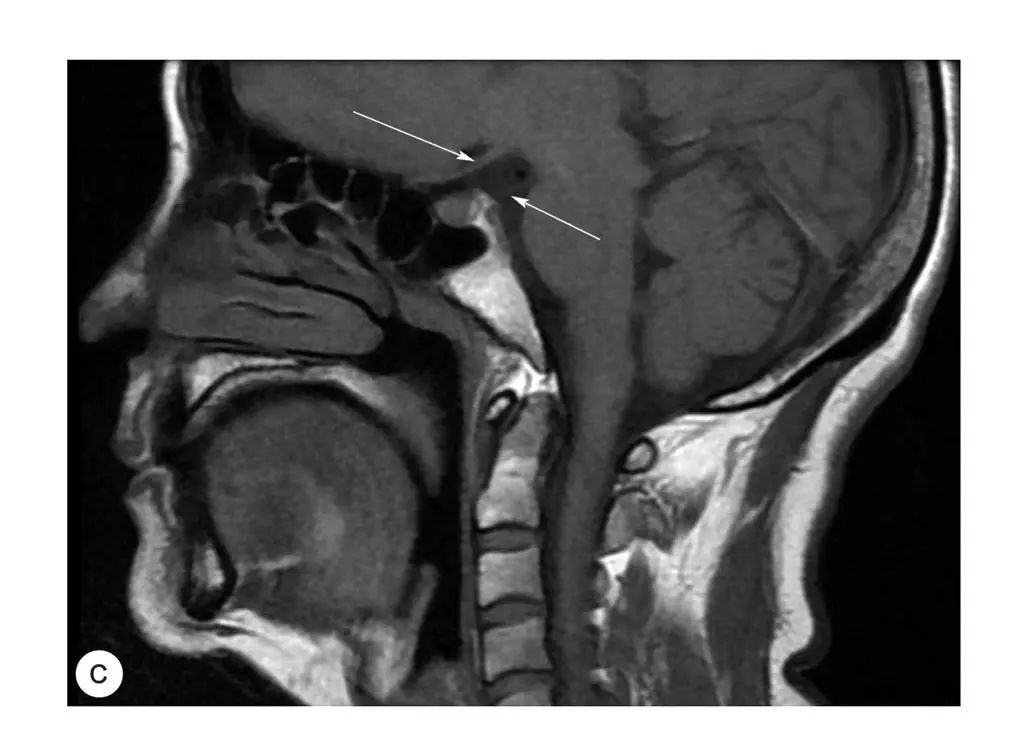

图2-19 舌下神经管及舌下神经出颅走行(MRI)

图2-20 舌下神经与颈静脉窝、椎体、乳突等周围结构的关系(CT冠状面)